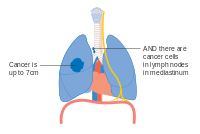

- Diagrams of main features of staging

Stage IA and IB lung cancer Stage IIA lung cancer

Stage IIA lung cancer Stage IIB lung cancer